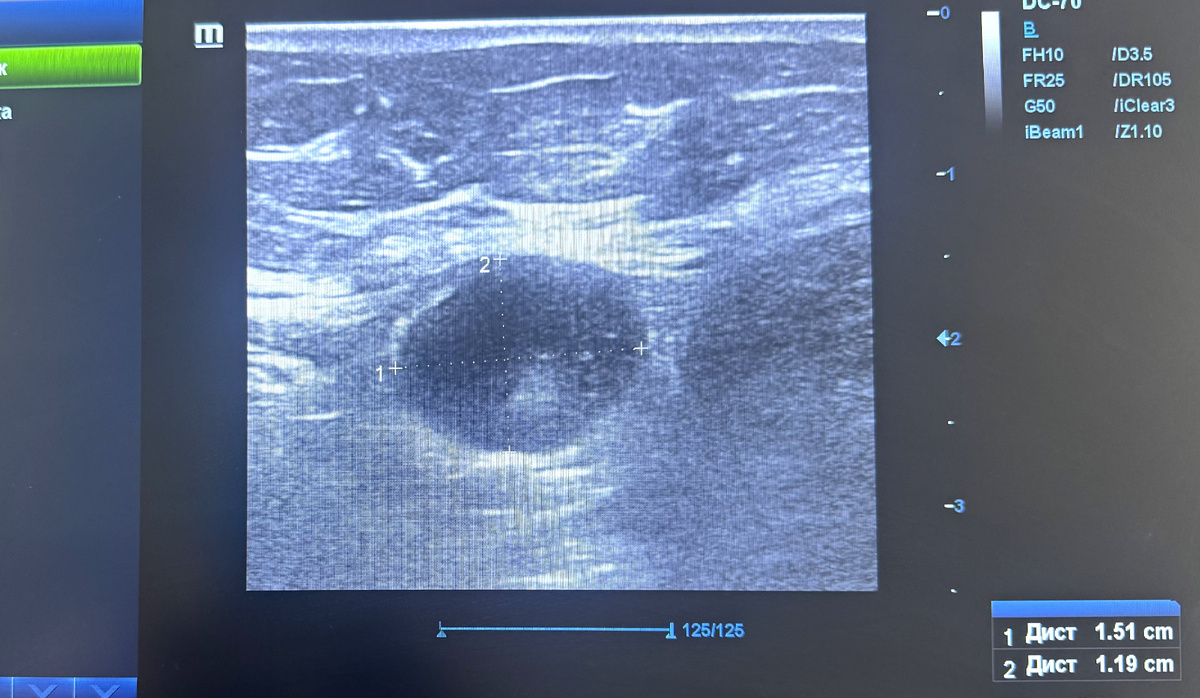

Так по УЗИ выглядит типичный метастатически измененный лимфоузел